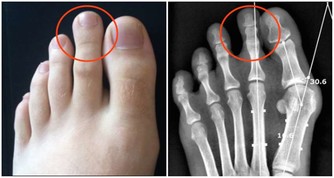

關節僵硬

晨僵的原因是由於在睡眠或活動減少時,使受累關節周圍組織滲液或充血水腫,

引起關節周圍肌肉組織緊張,而使關節腫痛或僵硬不適。

隨著肌肉的收縮,水腫液被淋巴管和小靜脈所吸收,晨僵隨之緩解。

可能導致晨僵的疾病包括:

強直性脊柱炎、類風濕性關節炎、腰肌勞損、風濕性多肌痛、軟組織損傷、椎管狹窄等。

因此,在出現晨僵症狀後應及時到醫院就診,查明病因並及時治療。